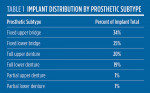

The distribution of implants used for each treatment modality is shown in Table 1. There were 2506 implants placed into the mandible and 3134 placed into the maxilla. Analysis of implant survival in the mandible and maxilla revealed similar survival rates of 93.1% and 91.3%, respectively. Survival based on each modality revealed that implants supporting partial lower dentures fared the best, with a survival rate of 95.6%, while those supporting full upper dentures fared the worst, with 85.2% survival (Figure 16).